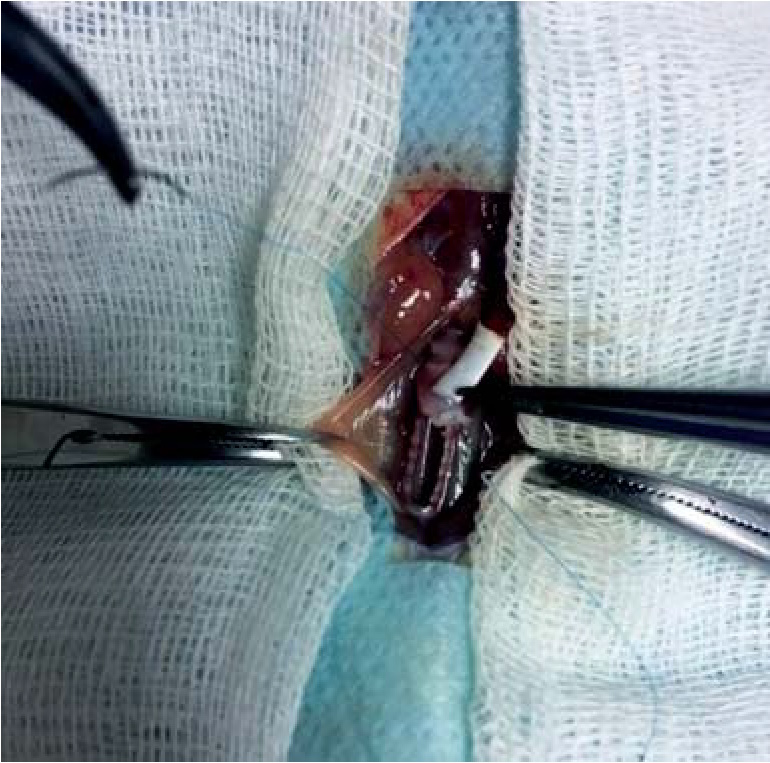

В ВМА активно развивается направление, связанное с пластикой экспериментальных дефектов органов и тканей, в частности трахеи (рис. 8) [9]. Для более успешной адаптации трансплантата в организме реципиента планируется закрытие дефектов двухслойным материалом, прекондиционированным in vivo, в целях его предсуществующей трансплантации реваскуляризации [11]. Совместно с ВИТ «ЭРА» выполняются исследования по трансплантации ацеллюлярной твердой мозговой оболочки, проводится поиск эквивалента биоинженерной кожи.

Рис. 8. Имплантация двухслойной биорезорбируемой заплатки в искусственно созданный окончатый дефект трахеи крысы